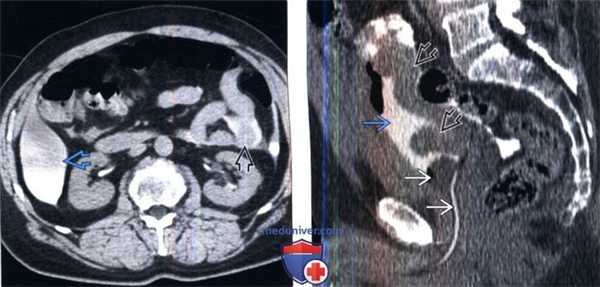

(Слева) КТ без контрастирования, аксиальный срез: у этого же пациента визуализируются почки, экскретирующие контрастируемую мочу, вследствие абсорбции контраста из внутрибрюшинной жидкости. Внутрибрюшинное скопление контрастируемой мочи контурируют петли малого кишечника и растягивает карман Морисона.

(Справа) Реконструкция КТ без контрастирования, сагиттальный срез: у этого же пациента определяется спавшийся мочевой пузырь, вследствие наличия катетера Фолея и интраперитонеальной экстравазации мочи, окружающей петли кишечника.

(Слева) КТ с контрастированием после цистографии, аксиальный срез: экстравазат контрастируемой мочи, окружающий матку, яичники и петли тонкого кишечника. Эти признаки характерны для внутрибрюшинного разрыва мочевого пузыря.

(Справа) КТ с контрастированием после цистографии, аксиальный срез: экстравазат контрастируемой мочи в околопузырных пространствах, вследствие внебрюшинного разрыва мочевого пузыря. Визуализируются несколько пузырьков газа глубоко в прямых мышцах живота, вследствие травмы мягких тканей и перелома таза.